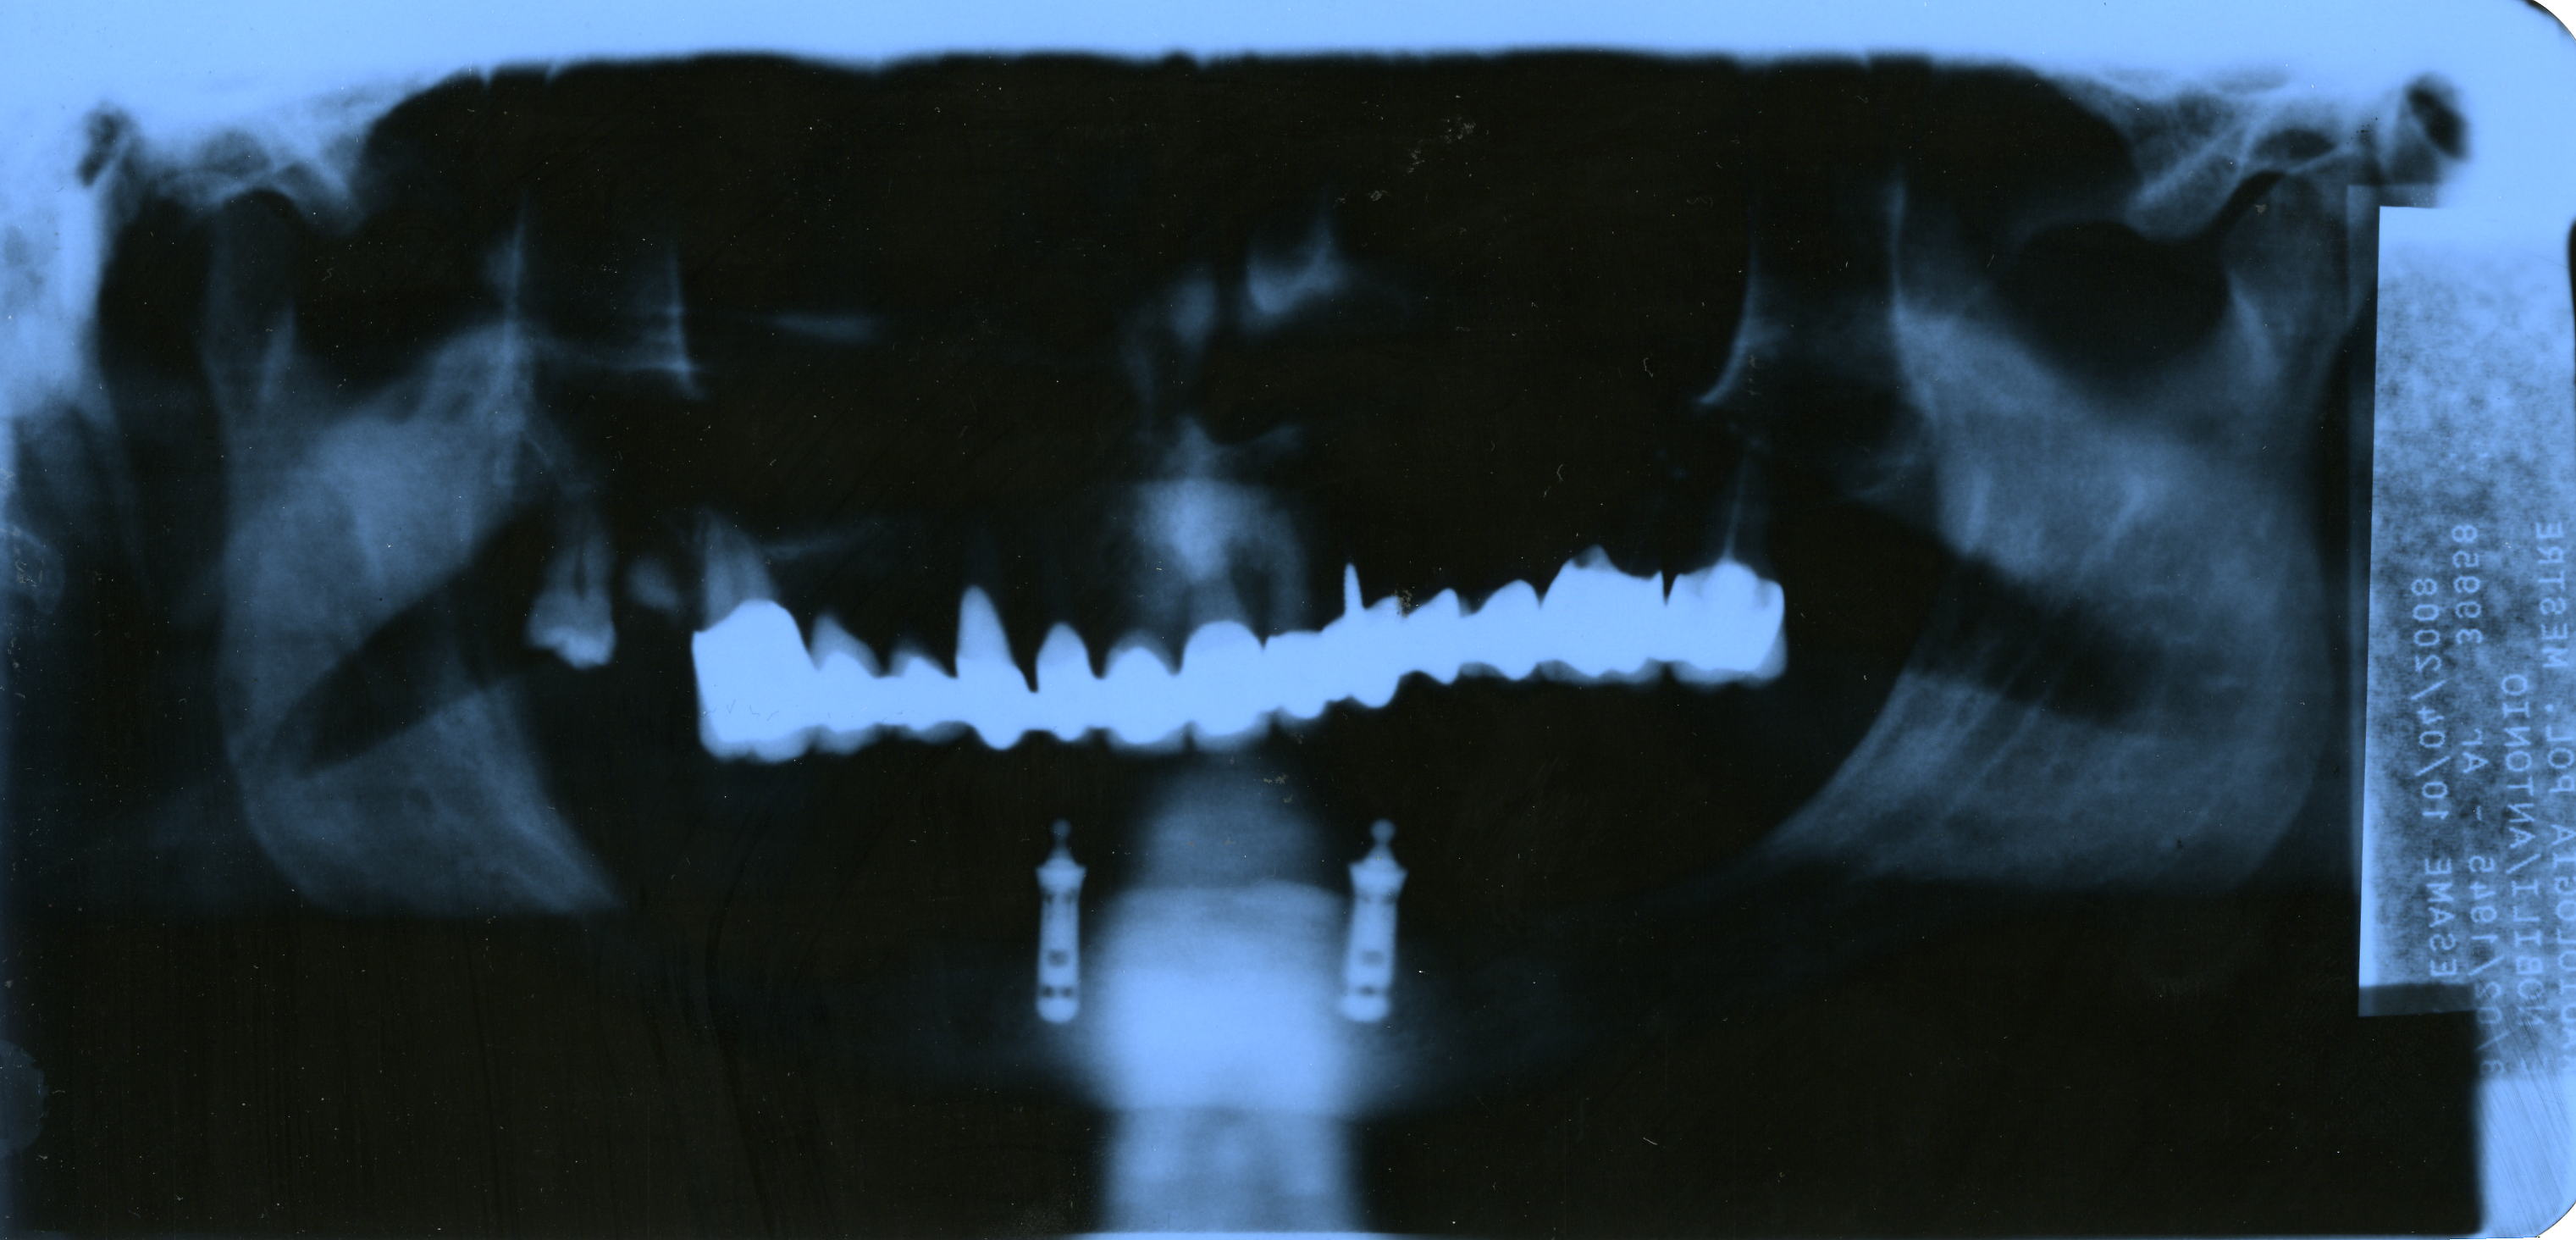

Dopo anni di protesi mobili e ultimo tentativo con 3 perni (centrale scomparso) sono ridotto ad una arcata inferiore nuda, ovviamente vivo in modo insopportabile. Sembra che consistenza ossea insufficiente. Possibile impianto fisso almeno per parte centrale (SEI DENTI? Grazie Vs attenzione. Vs parere mi conforterebbe. Abito a Mestre ed al momento non posso viaggiare.

Caro Antonio gli impianti nella rx sembrano degli Integral della Calcitec, un ottimo impianto anche se ormai datato, in una situazione clinica mediocre, necessitano indubbiamente di una robusta manutenzione per garantire un lungo lavoro. Ovviamente inserire altre fixture sarebbe vantaggioso oltre che auspicabile, poiche', piu' impianti = maggiore possibilita' di costruire una protesi duratura ed esteticamente valida. Naturalmente questi pensieri a voce alta necessitano di un approfondimento radiologico di uno step superiore, ed inoltre di un indispensabile esame clinico "de visu". Dott. Francesco Sacco Medico Chirurgo Odontoiatra Specialista in Chirurgia Maxilo Facciale in SALERNO e AVELLINO www.chirurgomaxillofacciale.it

Sig. Antonio, la sitazione a prima vista non è per una chirurgia semplice, in quanto per il forte riassorbimento dell'osso alveolare, il canale mandibolare nella zona molare è molto in alto, quindi anche i mini impianti non possono essere inseriti, pertanto bisogna fare della chirurgia ricostruttiva e poi pensare di inserire impianti in quella sede, mentre nella zona sinfisaria la cosa è possibile, anche se bisogna fare un dental scan, per valutare le dimensioni dell'osso disponibile, ma che attraverso artifizi chirurgici come split crest o altri è possibile inserire degli impianti per poter ancorare una protesi mobile o avvitata. NB: l'arcata sup. non è da meno. Dott. Maurizio Serafini

Caro Antonio, La radiografia non è molto chiara per poter dare delle valutazioni esatte e poi non è questo l'esame specifico. Comunque posso dirti che : Prima di tutto bisogna valutare in che condizioni sono i vari denti, perni o impianti che hai in bocca. Eventualmente ce ne fosse bisogno, li' dove ci siano dei problemi si procede con una bonifica. Poi con un esame Tomografico TAC, si valuta attentamente quanto osso rimane, quindi si decide per una riabilitazione bella bocca con impianti. L'osso, Antonio, se manca si può ripristinare con interventi aggiuntivi e, praticamente, non ci sono controindicazioni. Ovviamente devi valutare il medico, che dovra' essere un esperto di chirurgia orale e poi, cosa ancora piu importe, valutare prima il tuo stato di salute generale per vedere se sei idoneo a quanto detto oppure no. Distini saluti dott Giglio Andrea roma www.studiodentisticogiglio.it